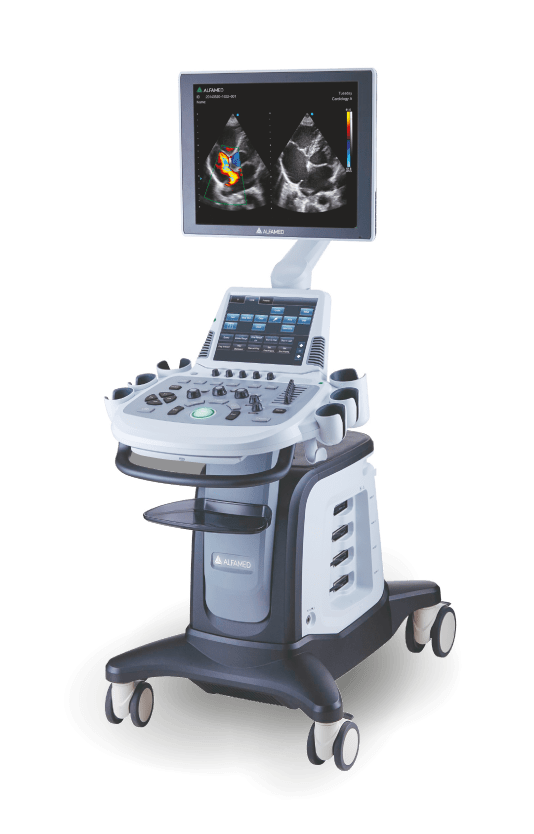

Magnus X5

Dotado de softwares avançados e transdutores específicos, o Magnus X5 apresenta alta versatilidade para imagem geral e excelente performance, principalmente, nos exames de cardiologia avançada e obstetrícia.

Possui design robusto, tela principal e tela touch screen de dimensões adequadas para melhor visualização da imagem e fácil manejo, painel de controle com ajuste de altura e rotação, favorecendo a ergonomia no momento do trabalho do profissional.